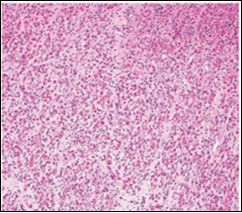

On microscopy, a collagen- rich, minimally cellular, fibrotic soft tissue nodule is exemplified which simulates a scar or conventional fibroma. The neoplasm is comprised of uniform, plump, fibroblastic or myo-fibroblastic cells encompassed in a collagen-rich stroma with infiltration and entrapment of skeletal myocytes 5, 6. Cogent histological examination depicts replacement of muscle fibres and muscle mass with fascicles of fibrous tissue comprised of mature fibroblastic cells, thereby conferring fibrosis 6. Figure 1, Figure 2, Figure 3, Figure 4, Figure 5, Figure 6, Figure 7, Figure 8.

Figure 3.Fibromatosis colli depicting fascicles of fibroblasts and myo-fibroblasts admixed with a collagenous stroma and extravasation of numerous red blood cells 10.